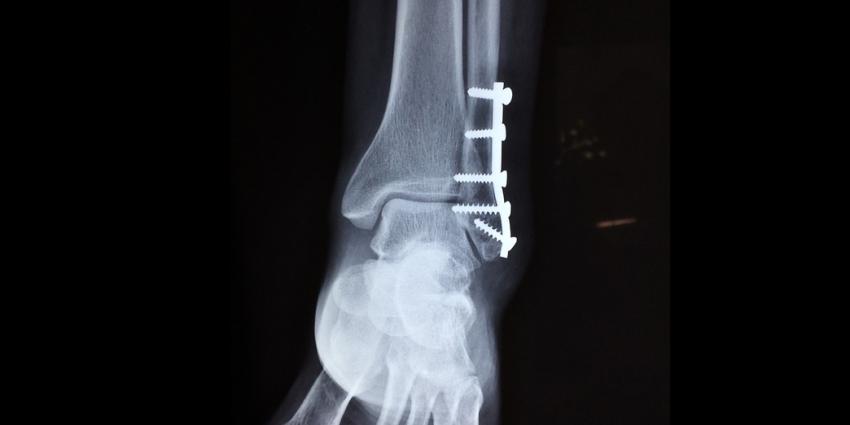

Bij wie een schroef of plaat uit hun been moet worden verwijderd heeft het toedienen van preventieve antibiotica geen enkele zin. 'Ze helpen niet tegen